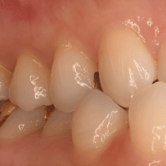

Dientes impactados

Los dientes impactados son dientes que no pueden erupcionar correctamente debido a la falta de espacio o a una obstrucción.

Los pacientes pueden notar que un diente no ha salido, aunque debería haberlo hecho. Esta condición es común con las muelas del juicio y los caninos superiores.

El tratamiento puede incluir la extracción del diente impactado o la creación de espacio para permitir su erupción.